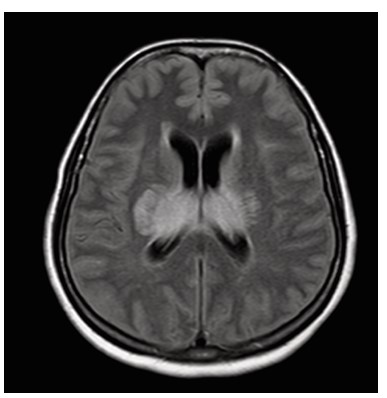

Dengue fever, a mosquito borne viral illness, is endemic in many parts of the world, particularly in tropical and subtropical regions. It is caused by four distinct serotypes (DENV 1–4) of single stranded RNA viruses from the Flaviviridae family. Although it is generally considered non-neurotropic, certain strains, especially DENV-2 and DENV-3, have been associated with neurological involvement. Neurological complications can include encephalopathy, encephalitis, meningitis, acute disseminated encephalomyelitis (ADEM), stroke, and Guillain-Barré syndrome. Dengue encephalitis, a relatively uncommon but serious manifestation, arises from direct viral invasion of neural tissue. This case report presents a patient with altered mental status and characteristic MRI findings symmetrical involvement of the thalami and cerebellum, known as the “double doughnut sign” indicative of dengue encephalitis. Cerebrospinal fluid analysis confirmed the diagnosis. Early recognition, neuroimaging, and supportive management with immunomodulation played a crucial role in the patient’s recovery. Clinicians should maintain a high index of suspicion for dengue encephalitis in endemic areas when encountering unexplained encephalopathy.